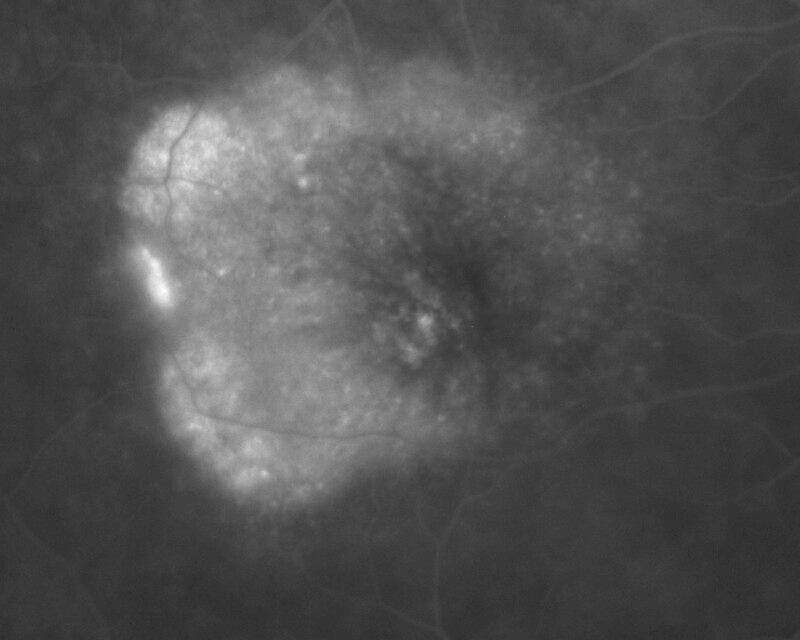

DSNE + DEP + NVO + PDT - 4 MOIS

IM000019.jpg